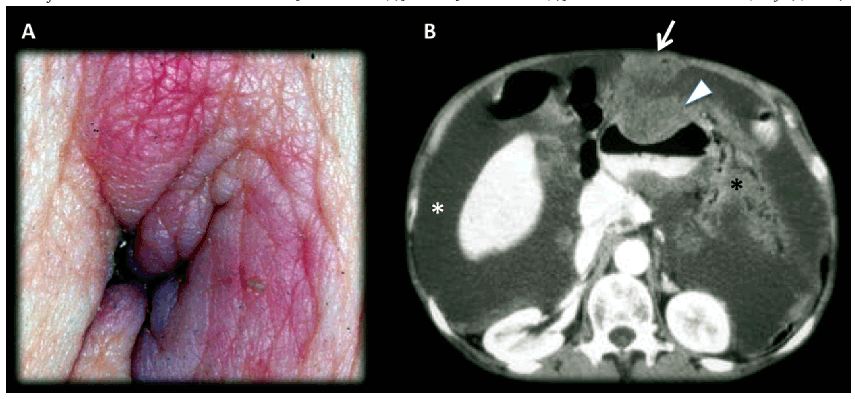

![Man 56 years old, advanced gastric neoplasm. A) Picture of the umbilical

lesion; B) Contrast enhanced MDCT axial slice, in portal-venous phase: Large

neoplastic lesion that bulge the anterior wall of the gastric wall (arrow head)

with transmural involvement with non-defined borders,

that invades the omentum [black asterisk (*)];

ascites [white asterisk (*)]; metastatic umbilical nodule (SMJN)(arrow).](../199358831007_gf3.png)